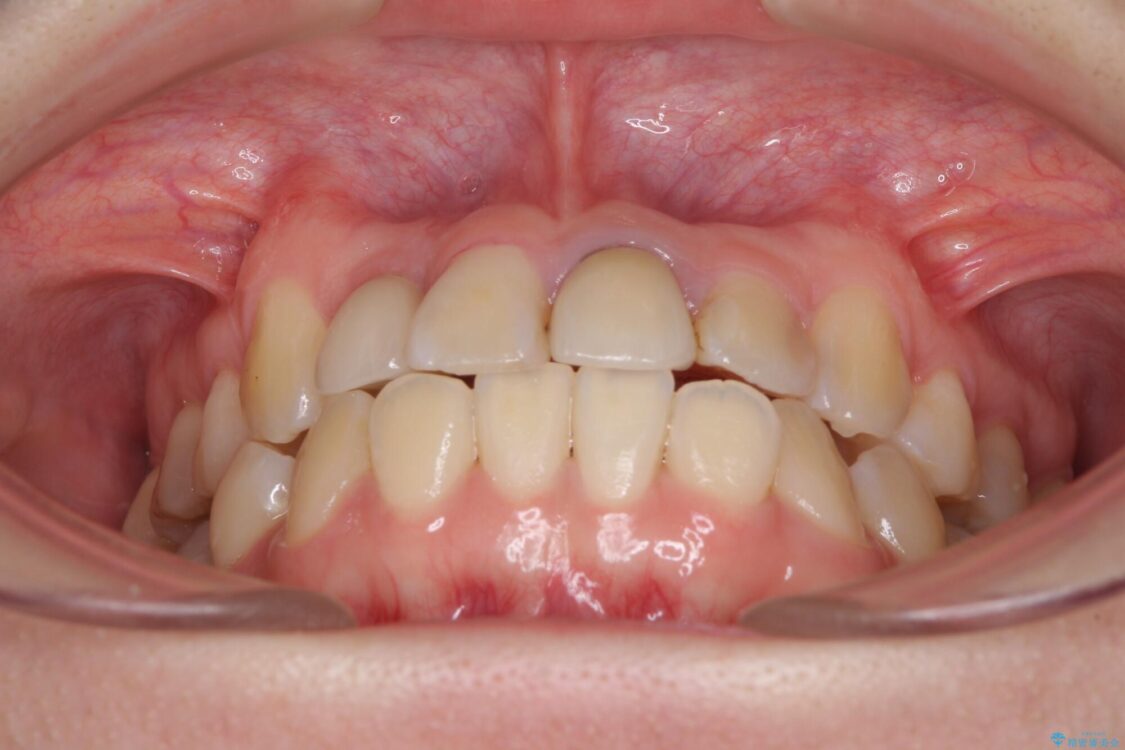

治療後

• 虫歯治療ついでに歯並びの後戻りを改善 インビザラインによる矯正治療 治療後画像